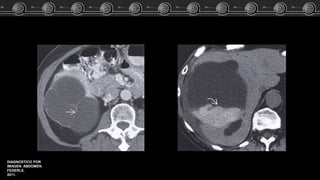

• Fase arterial: Captación

nodular periférica en fase

arterial, con captación lenta y

progresiva, centripeta e

isodensa respecto a los vasos.

• Fase venosa: Captación

progresiva, centripeta hasta el

relleno uniforme.

TC

DIAGNOSTICO POR

IMAGEN. ABDOMEN.

FEDERLE.

2011.